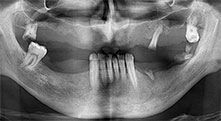

Pr Bratu : Nous utilisons couramment les instruments pour le prélèvement des blocs osseux et le clivage de la crête alvéolaire. Nous utilisons également les scies B6/B7 Piezomed pour l'ostéotomie des dents endommagées et l'extraction des implants défaillants. Bref, toutes les indications qui nécessitent des coupes profondes et propres.

Pr Bratu : Nous préférons prélever l'os sur la crête oblique externe de la mandibule postérieure, et non dans la région interforaminale. Après l'incision des tissus mous, nous utilisons les nouvelles scies pour définir la quantité d'os à prélever. De la même manière, nous les utilisons également pour la totalité de la préparation dans presque 80 % des cas. Nous avons également parfois recours à d'autres instruments piézoélectriques et, pour terminer, à un burin pour mobiliser le bloc. Nous trouvons cette technique chirurgicale très efficace.

Pr Bratu : Nous avons volontiers recours à la technique sandwich pour les augmentations mandibulaires latérales. La préparation d'un couvercle osseux est réalisée à l'aide de la scie piézoélectrique et le fragment crestal est fixé à l'aide de microvis. Nous plaçons un mélange de matériau de substitution osseuse autologue et xénogénique entre les deux. Cela fonctionne très bien. Il faut toujours s'assurer que les coupes verticales aient des dimensions suffisantes lors du clivage de la crête alvéolaire dans la mandibule. Sinon, l'os risque de se casser facilement.